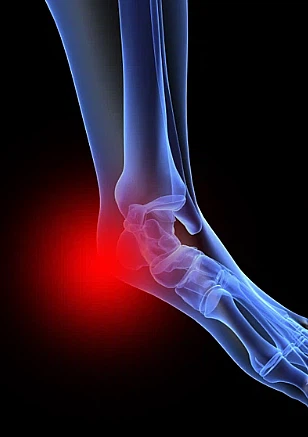

족저 근막염 증상 중 대표적인은 것은 오전에 일어나 처음 발을 내디딜 경우 느껴지는 심각한 진통이 특징입니다. 진통은 대부분 발뒤꿈치 안쪽에서 유발생하는 경우가 많습니다. 오전에 일어나서 발생하는 진통의 경우 수면 중 경직된 족저근막이 늘어나면서 발생하는 것으로 알려져 있습니다.

족저근막에 이상이 발생하면 발뒤꿈치에 진통이 나타납니다. 진통이 내부 깊숙한 곳으로부터 나타나는데, 증상이 심할 때는 발 전체가 아파 서있기도 힘듭니다.